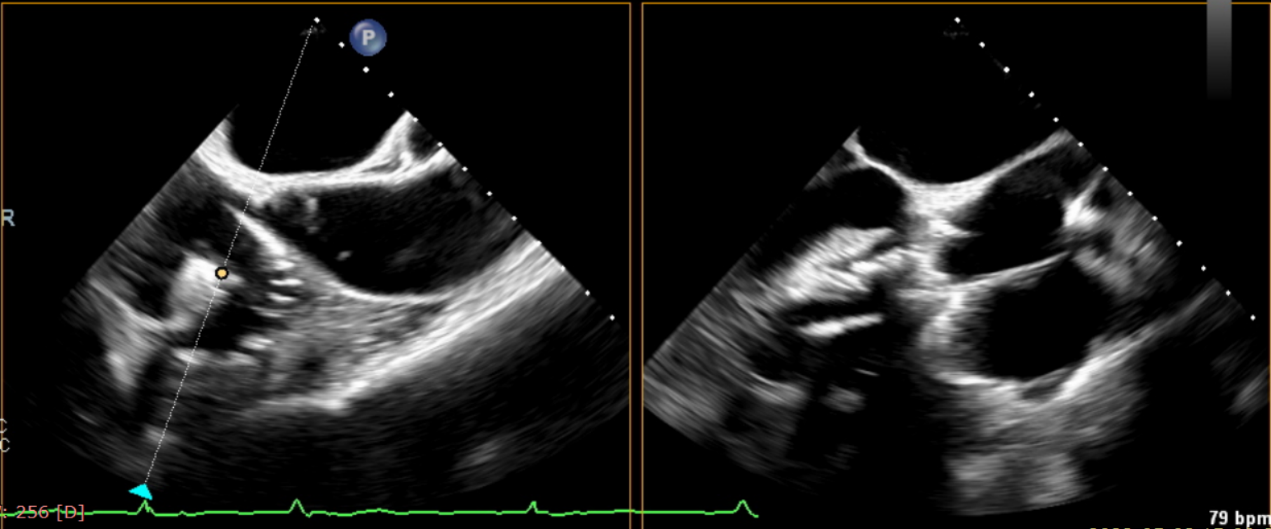

近日,美國紐約Montefiore醫(yī)學中心(Montrefiore Medical Center)的Azeem Latib教授團隊成功應用LuX-Valve Plus經(jīng)血管三尖瓣置換系統(tǒng)為兩位三尖瓣大量反流的患者完成三尖瓣置換手術。術后超聲顯示人工三尖瓣植入穩(wěn)定,瓣葉啟閉良好,僅殘余微量瓣周漏?;颊哂谑中g室即刻拔除氣管插管,血流動力學改善顯著。此次手術是LuX-Valve Plus于紐約的首次臨床應用,治療效果優(yōu)異。

術后Azeem Latib教授對LuX-Valve Plus經(jīng)血管三尖瓣置換系統(tǒng)的器械性能和治療效果大為稱贊,并且認為LuX-Valve Plus的手術體驗非常好。從治療效果來看,術后即刻超聲顯示三尖瓣反流幾乎完全消失,血流動力學改善顯著,患者恢復快。在面對復雜解剖結構、超聲影像質量不佳、有起搏導線干擾時,Lux-Valve Plus也體現(xiàn)了極強的適應性。Thomas Modine教授參與了術中指導,他同樣再次肯定了LuX-Valve Plus術中操作的便捷性,認為LuX-Valve Plus容錯率高,對術中影像的依賴小,并表達了后期希望可以更多地應用LuX-Valve Plus三尖瓣置換系統(tǒng)于臨床實踐,讓更多的三尖瓣重度反流患者盡早獲益,改善預后。